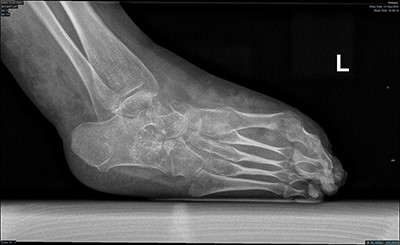

Magnetic resonance imaging (MRI) brain and whole spine were ordered for her due to the neurological pattern of the disease. The MRI showed T4–T5 posterior fusion, there were no other neurological lesions. For evaluation of the varicose veins, vascular consultation was obtained, and Doppler ultrasound was ordered, which showed absent popliteal deep veins. Radiography of the left foot revealed marked cavus as well as hindfoot and forefoot varus. Also, it showed soft tissue swelling, reduction in bone density, and no evidence of fracture or dislocation or tarsal coalition (Fig. 2). The right foot radiograph was unremarkable apart from mild hallux valgus deformity (Fig. 3).

Lateral weight bearing radiograph showing severe pes cavus with osteopenia and soft tissue swelling.